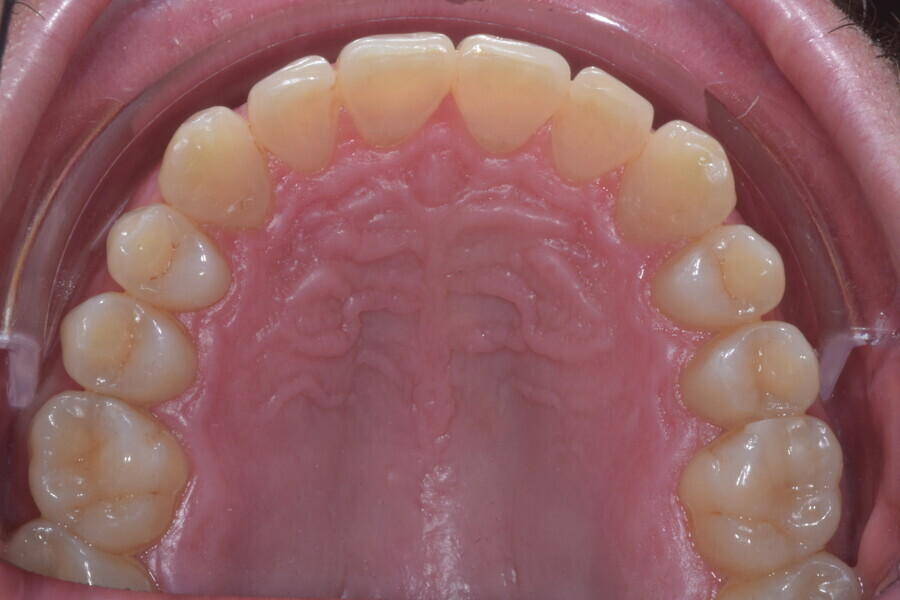

Le motif principal de consultation de ce patient âgé de 37 ans, était de rétablir l’alignement des dents antérieures sur les deux arcades. L’analyse faciale a indiqué une face courte avec un profil plat, mais une projection normale du menton (Figs. 9–12), et l’examen clinique a révélé une classe squelettique de type I (angle ANB = 0,89°) et une malocclusion de classe I avec supraclusion sévère (près de 100 %), une courbe de Spee très prononcée, un torque normal de l’incisive centrale supérieure (Ui-FH = 110°), un encombrement dentaire léger sur l’arcade maxillaire et modéré sur l’arcade mandibulaire (Figs. 13–18). Chez ce patient, les composantes de la supraclusion correspondaient à une dysmorphie squelettique grave correspondant à une hypodivergence (FMA = 14,24°), avec une inclinaison normale des incisives supérieures et inférieures et un angle goniaque réduit (110,46°). L’analyse du cliché céphalométrique indiquait une hauteur réduite de l’étage inférieur de la face associée à l’hypodivergence (Fig. 19). La seule option de traitement envisagée était un traitement orthodontique par aligneurs avec tous les éléments auxiliaires décrits (rampes d’occlusion, zones de pression, nivellement de la courbe de Spee dans les trois dimensions, élastiques de classe II et puissants contacts occlusaux) afin de corriger la supraclusion.

Le plan de traitement numérique (ClinCheck) avait prévu douze aligneurs pour l’arcade maxillaire et dix-sept pour l’arcade mandibulaire. Les objectifs du traitement visaient à combiner les mouvements verticaux d’extrusion des dents postérieures et les mouvements d’intrusion des dents antérieurs, au moyen de rampes d’occlusion, tout en utilisant des taquets d’extrusion pour assurer la désocclusion des dents postérieures et l’intrusion des dents antérieures inférieures, nécessaires au nivellement de l’arcade mandibulaire. La courbe de Spee a été nivelée et le profil plat ainsi que la position des lèvres ont été améliorés par une vestibulo-version des incisives supérieures et inférieures. Le plan avait prévu des élastiques de classe II pour faciliter la vestibulo-version des dents inférieures et les puissants contacts occlusaux postérieurs, avec une extrusion relative des dents postérieures. Une morphologie plus large de l’arcade et une intercuspidation idéale ont été obtenues par des mouvements de torque proches de 0° des dents latérales et postérieures supérieures. Aucune conception technique excessive n’avait été prévue dans le plan de traitement numérique. En raison de l’âge du patient, les aligneurs ont été changés tous les dix jours, dans le cadre d’un traitement d’une durée inférieure à six mois. À la fin de la première série d’aligneurs (Figs. 20–24), un nouveau plan de traitement numérique comportant cinq autres aligneurs a été conçu, en vue d’améliorer l’intercuspidation des molaires sans élastiques. La durée totale du traitement a donc été prolongée jusqu’à 7,5 mois puisque les aligneurs supplémentaires étaient changés toutes les semaines.